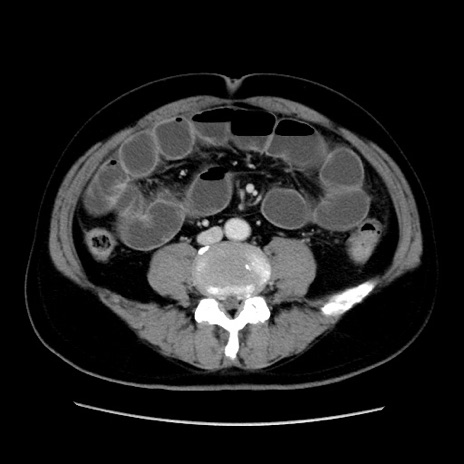

冠状断像

症例16(横断像)

【症例】 70歳代男性

【主訴】 腹痛、嘔吐

【現病歴】 約1ヶ月前より間欠的に腹痛と嘔吐あり、当院消化器内科を受診したところCTで多発する肝臓のLDAを指摘され、精査中であった。以降は消化器症状は安定していたが、2日前より嘔気と腹痛があり、同日より排便・排ガスが消失した。改善認めず、 本日、救急外来を受診した。

【既往歴】 大腸ポリープ切除後。

【身体所見】意識清明・会話良好、BT 36.3℃、BP 127/80mmHg、 P 80bpm、腹部:膨満あり、平坦・軟、上腹部正中および下腹部正中に圧痛あり、反跳痛なし、筋性防御なし。

【データ】WBC 7200、CRP 0.77